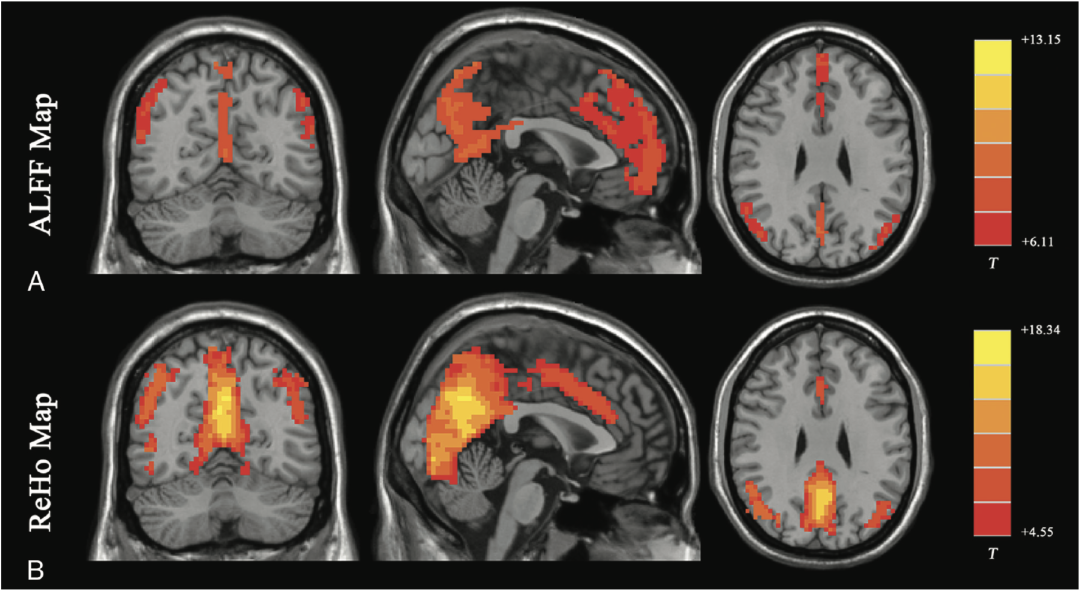

科学家早就证明,大脑一直在全力工作,不存在大脑某个部分“100%”不工作。即使是在休息或者睡觉的时候,脑子也没有停下来,而是在处理记忆、情感和维持身体的基本功能。用先进的神经成像技术,比如功能性磁共振成像(fMRI),我们可以清楚地看到大脑的不同区域在执行不同任务时都在活跃着。

来自参考资料[1]:健康志愿者静息状态下大脑的活跃度,颜色越深越活跃

这个谣言被广泛相信,可能是因为人们对大脑的复杂性不了解,觉得还有很多“潜能”没被开发。但实际上,正因为大脑的工作机制非常复杂,我们在不知不觉中就用到了它的各个部分。你看到的每一个画面、想到的每一个点子,甚至是控制心跳和呼吸,都是大脑在背后辛勤运作的结果。